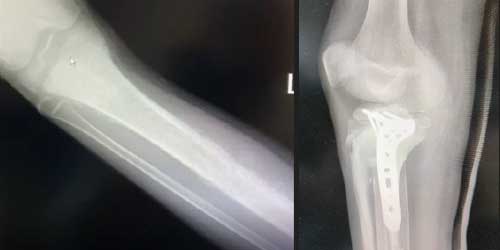

Omurga metastazı, kanserin ilk olarak iç organlarda gelişip daha sonra omurga kemiklerine yayılması sonucu oluşan bir durumdur. Çoğunlukla kan yoluyla sıçrayan bu tür metastaz, hastalarda sırt ve bel ağrısı gibi şikayetlerle kendini gösterir. Erken teşhis ve uygun tedavi yöntemleri, hastaların yaşam kalitesini artırmada kritik bir rol oynar.

Tedavide başarıyı artıran en önemli etkenlerden biri ameliyat öncesi iyi bir hazırlık ve cerrahi planlama yapmaktır. Her şeyden önce tanı doğru konmalı. Bunun için hasta iyi dinlenip, detaylı muayene edildikten sonra tetkikleri dikkatli incelenmelidir.